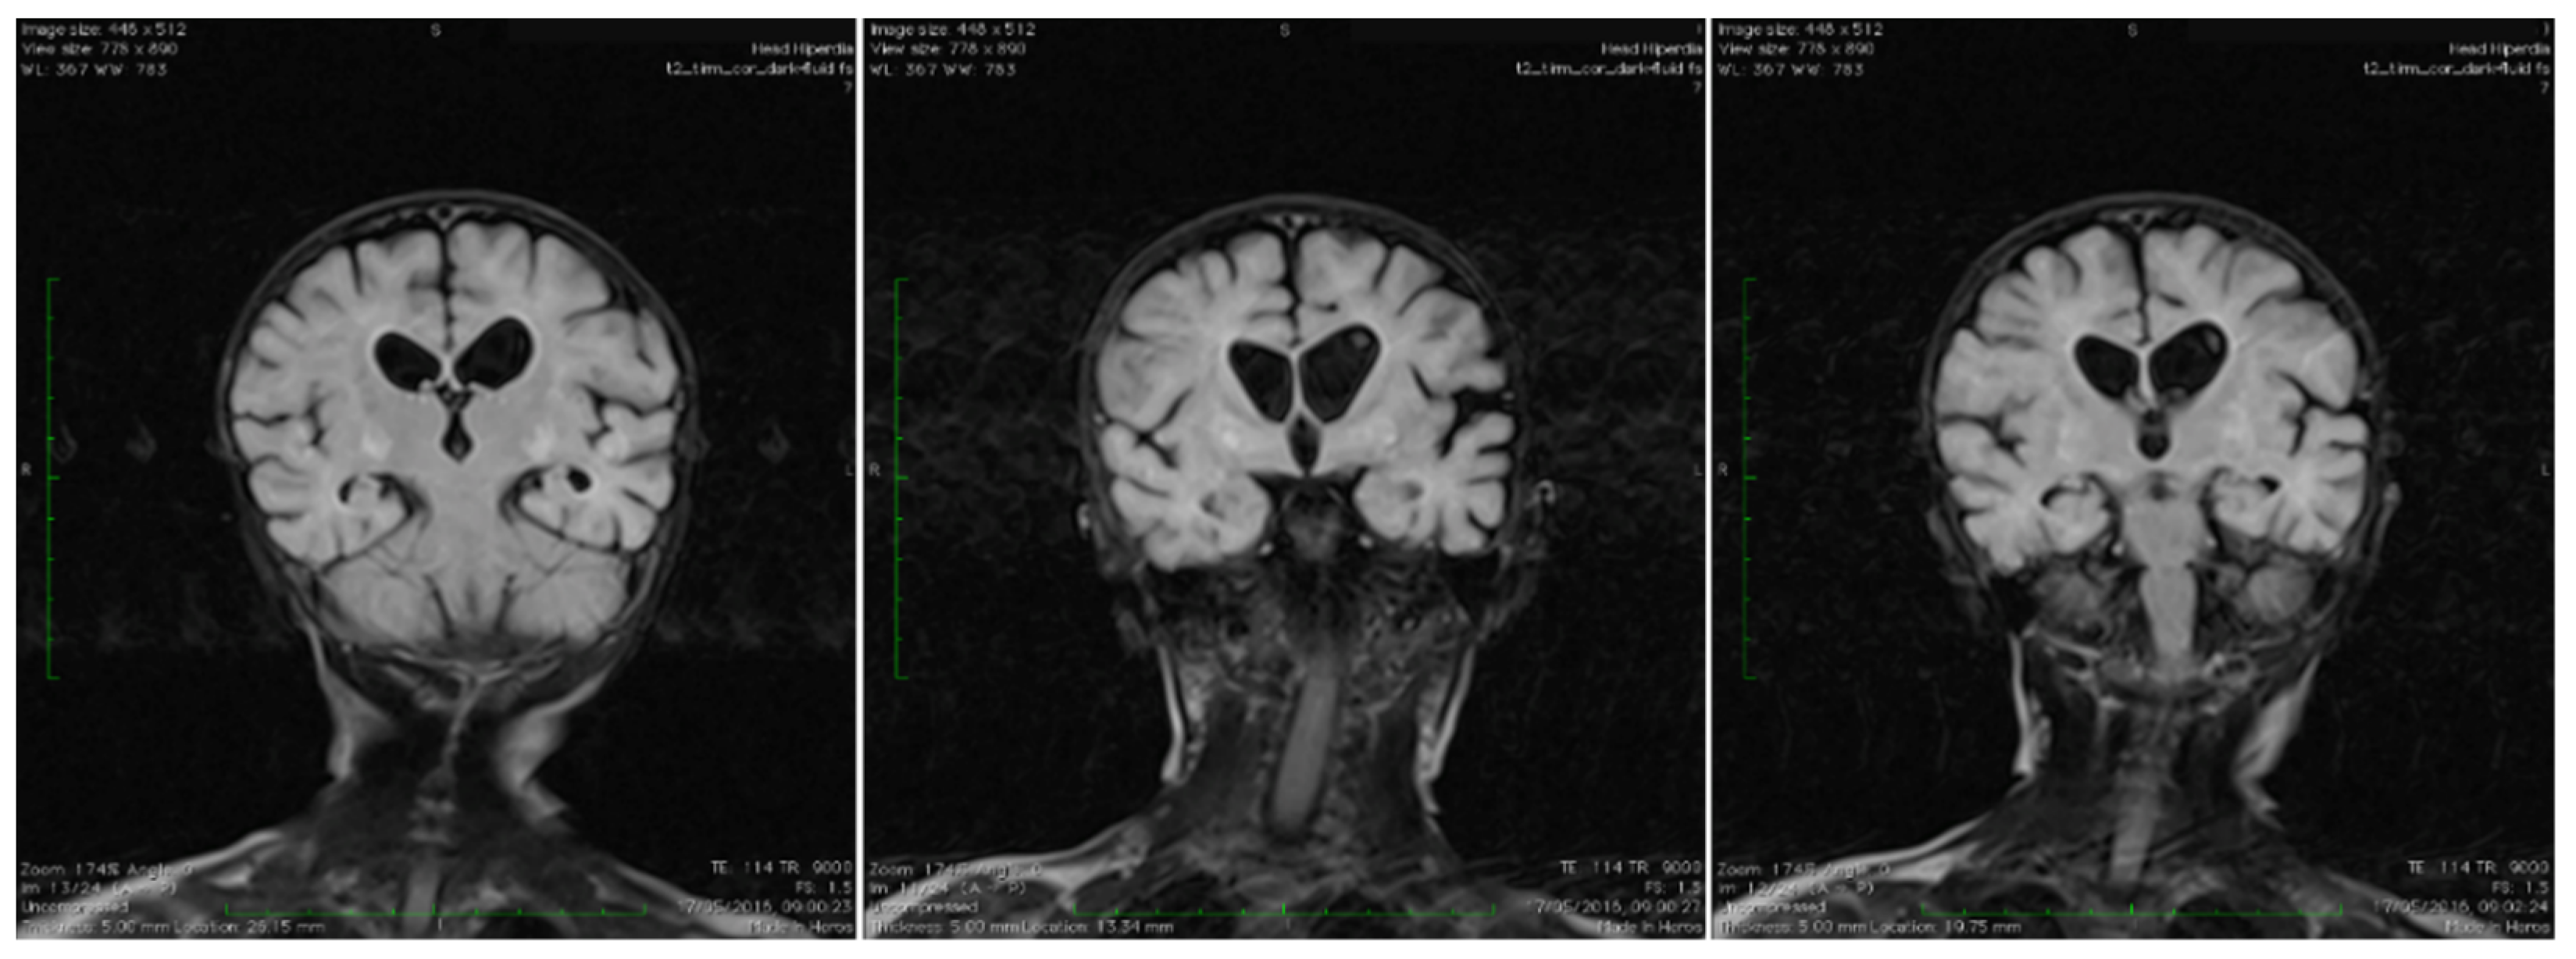

| MRI changes | brain atrophy, hyperintensity within putamen, cavitation at this level, extensive diffuse white matter changes | atrophy of the cerebellum and brain stem, mild ventricular dilatation, generalized atrophy of the grey matter, thinning of the corpus callosum | moderate brain atrophy, low intensity in cerebral white matter | Extensive brain atrophy, widening of the subarachnoid space and of the ventricular system | no atrophy, hyperintensity in nucleus caudatus and putamen | cerebellar atrophy, hyperintense T2-weighted images in the putamen, globus palidus, caudate nuclei | regions of increased T2 and FLAIR signal and of hypointense T1 signal in the globus pallidus bilaterally with mild diffusion restriction | globus pallidus, putamen, caudate nuclei, basal ganglia T2 hyperintensity | asymmetric ventricular dilatation, partial agenesis of the posterior part of the corpus callosum, basal ganglia, a slight increase of T2 WM signal intensity, germinal cyst in the thalamo-caudate notch | asymmetric cavitation of globus pallidus, bilateral T2-WI hyperintensity, restricted diffusion | globus pallidus, caudate nuclei T2 hyperintensity |